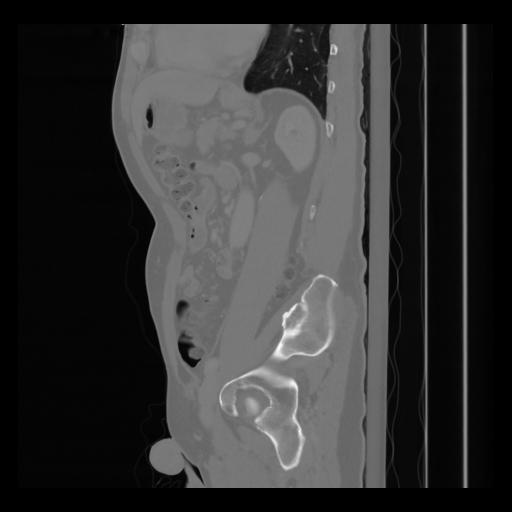

36 CUERPO,CE,Sagittal,3.000,CUERPO,Sagittal,